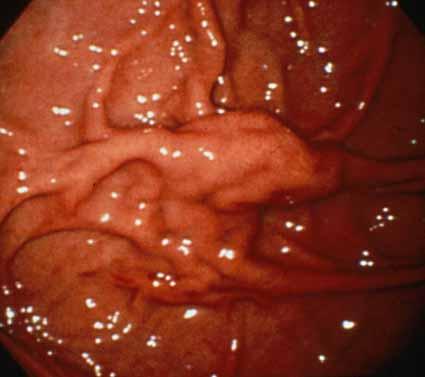

大きな胃粘膜下腫瘍様の所見を呈したアニサキス症の内視鏡像(初回より7日後)  (ID:312)の写真で示した病変部を拡大してみたものです。1本のひだが限局性に腫大した所見になっております。またその周辺の粘膜ひだも、軽度腫大しております。これらの表面には、わずかに発赤しておりますが、初回時にみられました不整な地図状の出血斑は消失しております。

疾患(病理主体)の分類寄生虫疾患/アニサキス

部位(臓器別)胃(部位)/その他

検査方法内視鏡